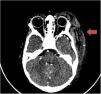

We present the case of a boy aged 16 months who presented with a blue-black hemorrhagic plaque in the left parieto-occipital region extending to the eyelid and earlobe and had appeared eight hours before (Fig. 1A). There was no history of traumatic injury. Upper respiratory tract infection preceded its development. The patient was afebrile, in good general health, without hematomas, petechiae or ecchymosis in other locations. The salient laboratory findings were thrombocytopenia (49 000 platelets/μL) and severe coagulopathy with absence of coagulation (undetectable) and a D-dimer level of 976 mg/L. There were no signs of malignancy or hemolysis. The patient also had leukocytosis with neutrophilia and slight elevation of acute phase reactants. The chest radiograph revealed nonspecific bilateral perihilar infiltration. The examination of the lesion by Doppler ultrasound and cranial CT confirmed the presence of extra-axial cephalohematoma in absence of intracranial bleeding or thrombosis.